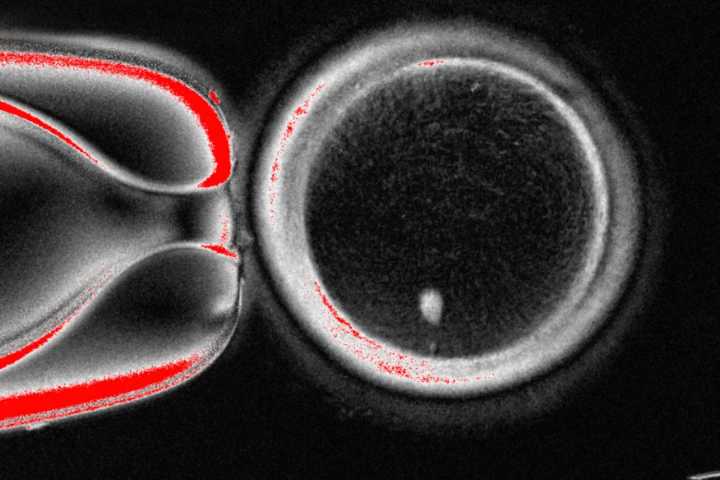

The OHSU team removed the nucleus from a human egg cell and replaced it with the nucleus from a human skin cell. But a skin cell contains two sets of chromosomes